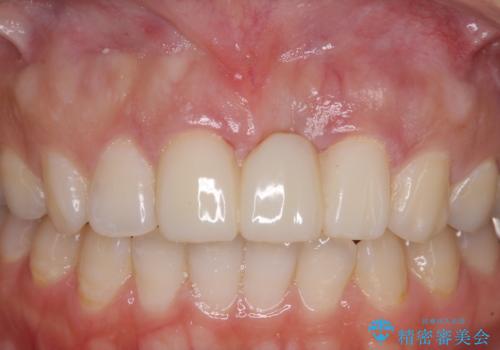

前歯のブリッジが気に入らない 歯肉移植術を併用した前歯のブリッジ

- 接着タイプの前歯のブリッジが不自然であるとのことで来院された患者様です。

欠損部の歯肉が窪んでいるため、歯肉移植により形態を改善し、オールセラミックブリッジにて補綴することとしました。